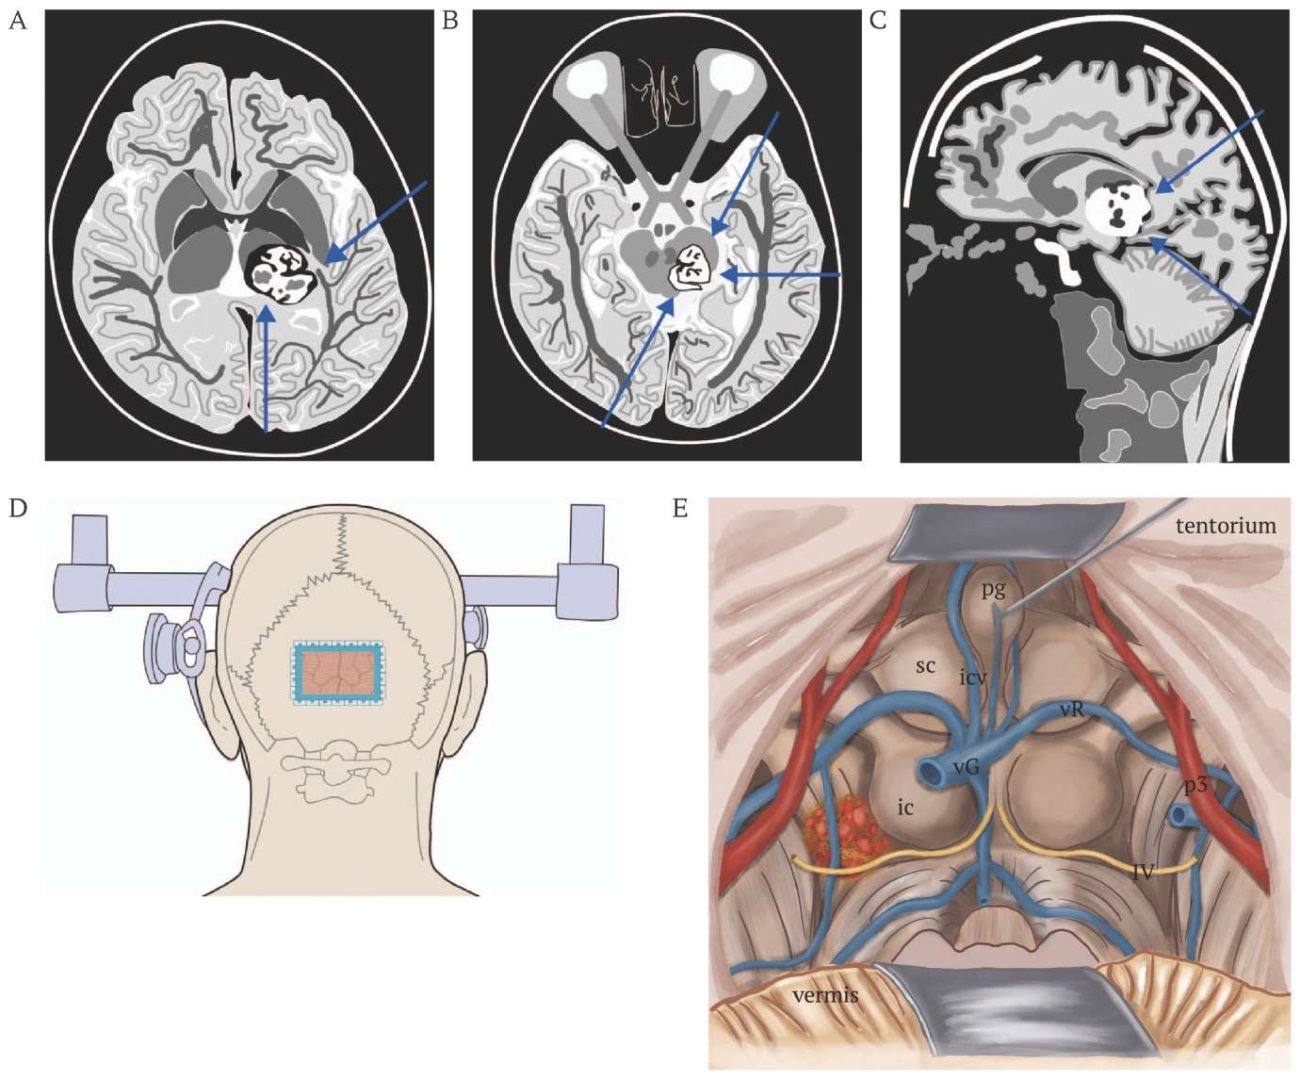

To avoid any postoperative neurological deficit (as assessed by additional scales: 4 points on the Spetzler–Martin [11] and 3 points on the Lawton–Young [12]), a median suboccipital craniotomy with a contralateral supracerebellar infratentorial approach was chosen for radical cavernoma resection (Fig. 2A–E).

FIG. 2. Schematic representation of the localization of the cavernoma of the dorsal surface of the midbrain and the choice of strategy for its resection.

A. Axial section. The arrows indicate the approaches to the midbrain: left lower – supracerebellar infratentorial; right upper – posterior subtemporal.

B. Axial section. The arrows indicate the approaches to the midbrain: left lower – contralateral supracerebellar infratentorial; right upper – anterior subtemporal; right lower – posterior subtemporal approaches.

C. Sagittal section. The arrows indicate the approaches to the midbrain: right upper – occipital transtentorial; right lower – supracerebellar infratentorial.

D. Exposure of the cavernoma using torcular craniotomy and supracerebellar infratentorial approach (blue line).

E. Access to the cavernoma through the supracerebellar infratentorial plane and the quadrigeminal cistern; identification of the ascending deep cerebral veins; determination of the feeding arteries of the pons and midbrain; review of the lateral sections; dissection of the quadrigeminal cistern to provide a free corridor (superior view of the midbrain, pons, tentorium from the pineal region and superior cerebellar peduncle); mobilization of the vessels and veins draining into the superior sagittal sinus.

Note: ic – inferior colliculus; icv – internal cerebral vein; pg – pineal gland; p3 – posterior cerebral artery (segment p3); sc – superior colliculus; vG – vein of Galen; vR – vein of Rosenthal; IV – cranial nerves (IV pair).